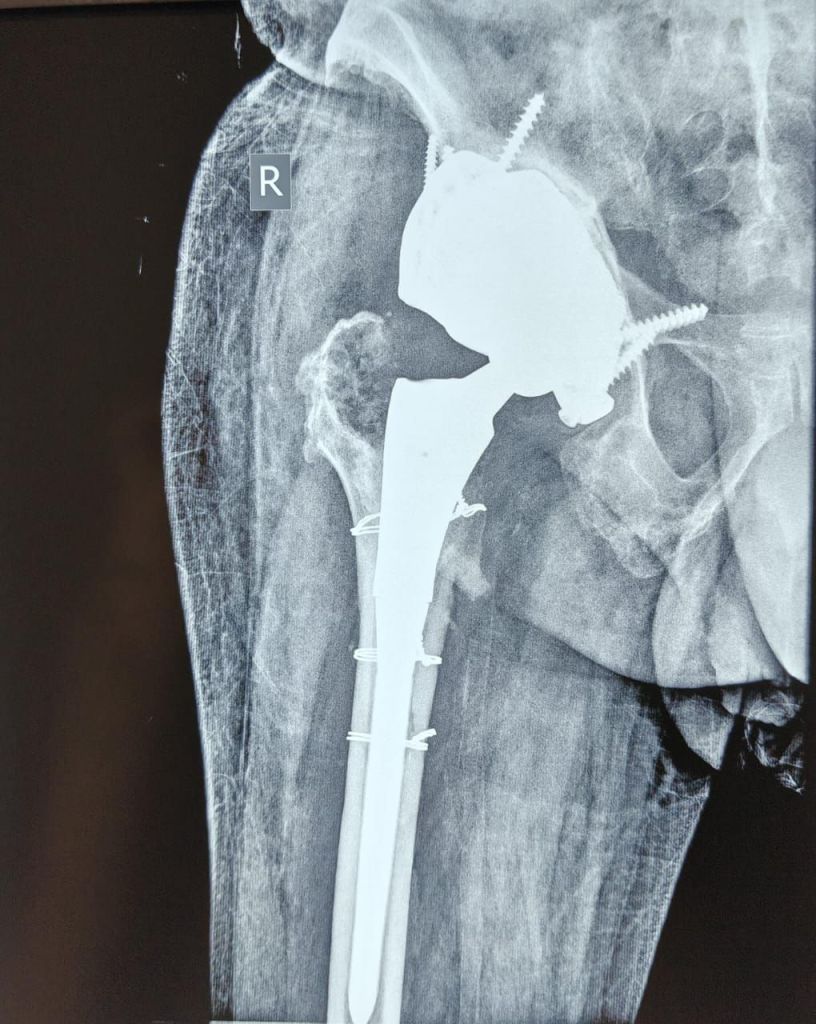

यहां विशेषज्ञ डॉक्टरों की टीम द्वारा तमाम जरूरी जांच के बाद यह स्पष्ट हुआ कि उनके कुल्हे की हड्डी में एक बहुत बड़ा दोष (बोनी डिफेक्ट) है, जिसे सामान्य इम्प्लांट्स से ठीक कर पाना संभव नहीं था। ऐसे में मरीज के लिए विशेषरूप से डिजाइन किया गया 3D प्रिंटेड कस्टमाइज्ड इम्प्लांट तैयार कराया गया।

बीते फरवरी माह के अंतिम सप्ताह में प्रोफेसर रूप भूषण कालिया के मार्गदर्शन में ऑर्थोपेडिक्स विभाग की टीम द्वारा 8 घंटे में यह जटिल सर्जरी को सफलतापूर्वक अंजाम दिया गया। डॉ. रूप भूषण कालिया के अनुसार इस प्रक्रिया में पहले से डाले गए सीमेंट स्पेसर और नेल को हटाकर 3D प्रिंटेड कस्टम इम्प्लांट को प्रत्यारोपित किया गया। राज्य में हुई यह अपनी तरह की पहली जटिल सर्जरी के लिए सहयोगी एनेस्थीसिया टीम का नेतृत्व डॉ. भावना गुप्ता ने किया।

सर्जरी के 7 सप्ताह बाद अब पेशेंट संदीप शर्मा पूरी तरह वजन सहन करने की स्थिति में हैं और उन्होंने सामान्यरूप से चलना प्रारंभ कर दिया है।